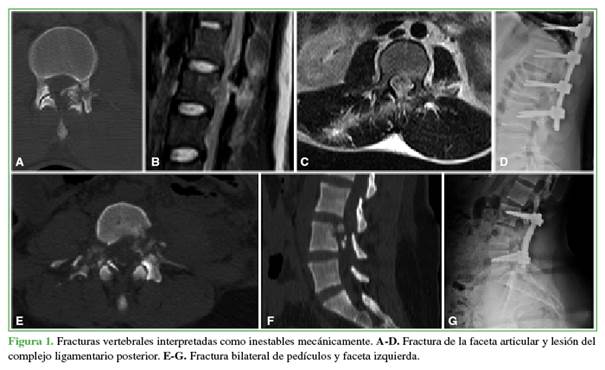

Con respecto a la inestabilidad mecánica, no existe un consenso en la bibliografía para definir inestabilidad en lesiones vertebrales por proyectil de arma de fuego; asimismo, es controvertido aplicar los mismos criterios que para fracturas por trauma cerrado.10,11 Por tal razón, en el estudio retrospectivo de las imágenes, se consideró como inestables a aquellas fracturas con evidencia de desplazamiento, compromiso ligamentario, compromiso bilateral de pedículos o facetas articulares (Figura 1).11

Todos los casos eran consecuencia de agresiones por proyectiles de baja velocidad. El orificio de entrada era torácico en el 45% (n = 10) de los pacientes, seguido de la cabeza y el cuello (n = 7; 32%). En 12 casos (54%), no se registró un orificio de salida del proyectil. La incidencia del proyectil era predominantemente no penetrante (n = 7; 32%) o transfixiante (n = 6; 27%); seguida de tangencial penetrante (n = 5; 23%) y penetrante (n = 4; 18%). En cinco (23%) pacientes, se constató el proyectil (n = 4) o sus fragmentos (n = 1) alojados en el canal vertebral. La lesión vertebral se consideró inestable en seis (27 %) casos. La descripción de la muestra se resume en la Tabla 1.